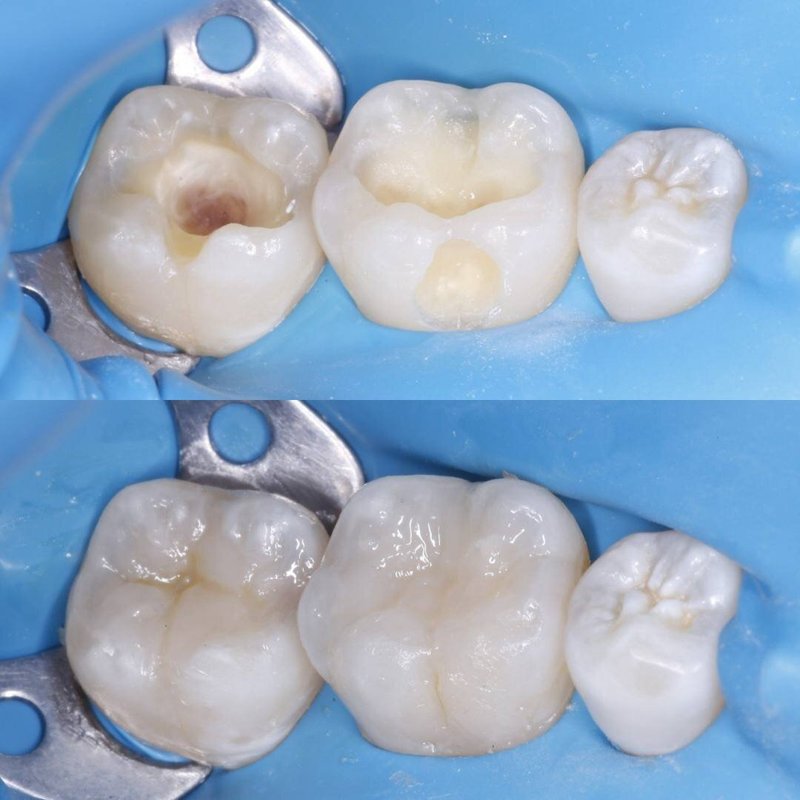

Фотогалерея